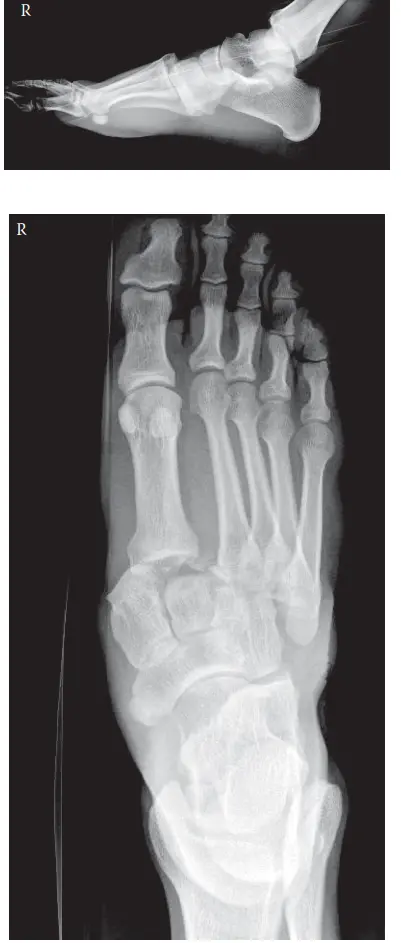

1. الأشعة السينية الأولية (Initial Radiographs)

تُعد الأشعة السينية هي الخطوة الأولى في تقييم إصابات القدم. في حالة إصابة ليزفرانك، غالبًا ما لا يمكن الحصول على أشعة سينية مع تحمل الوزن بسبب الألم الشديد وعدم قدرة المريض على الوقوف. لذلك، يتم الحصول على أشعة سينية للقدم المصابة بدون تحمل وزن، بما في ذلك:

* المنظر الأمامي الخلفي (AP View): يُظهر القدم من الأمام.

* المنظر الجانبي (Lateral View): يُظهر القدم من الجانب.

* المنظر المائل بزاوية 30 درجة (30-degree Oblique View): يُظهر القدم بزاوية لمشاهدة المفاصل الجانبية.

صورة بالأشعة السينية تظهر توسعًا بين مشط القدم الأول والثاني وعلامة فليك

النتائج الرئيسية التي يبحث عنها الأطباء في الأشعة السينية:

• في المنظر الأمامي الخلفي (AP View):

• توسع المسافة بين قاعدتي مشط القدم الأول والثاني: إذا زادت هذه المسافة عن 2.5 ملم، فهي علامة قوية على إصابة ليزفرانك.

• فقدان المحاذاة: يجب أن يتطابق الحد الإنسي (الداخلي) لعظم مشط القدم الثاني مع الحد الإنسي للعظم الإسفيني الأوسط. أي انحراف عن هذا التوافق يشير إلى إصابة.

• "علامة فليك" (Fleck Sign): وهي عبارة عن كسر قلعي صغير (قطعة عظمية صغيرة منفصلة) من قاعدة مشط القدم الثاني أو العظم الإسفيني الإنسي. هذه العلامة تدل بوضوح على تمزق رباط ليزفرانك.

• إزاحة جانبية خفيفة: قد يلاحظ إزاحة جانبية لعظام مشط القدم من الثاني إلى الخامس.

• في المنظر الجانبي (Lateral View):

• إزاحة ظهرية (للأعلى): قد يظهر إزاحة قاعدة مشط القدم الثانية للأعلى مقارنة بالعظم الإسفيني الأوسط.

• اضطراب في قوس منتصف القدم: يمكن استنتاج اضطراب في شكل قوس القدم الطبيعي.

• في المنظر المائل (Oblique View):

• إزاحة جانبية: يظهر إزاحة جانبية لعظام مشط القدم الثالث والرابع والخامس من مفاصلها مع العظام الإسفينية والمكعبي.

• فقدان المحاذاة: يجب أن يتطابق الحد الإنسي لعظم مشط القدم الرابع مع الحد الإنسي للعظم المكعبي.